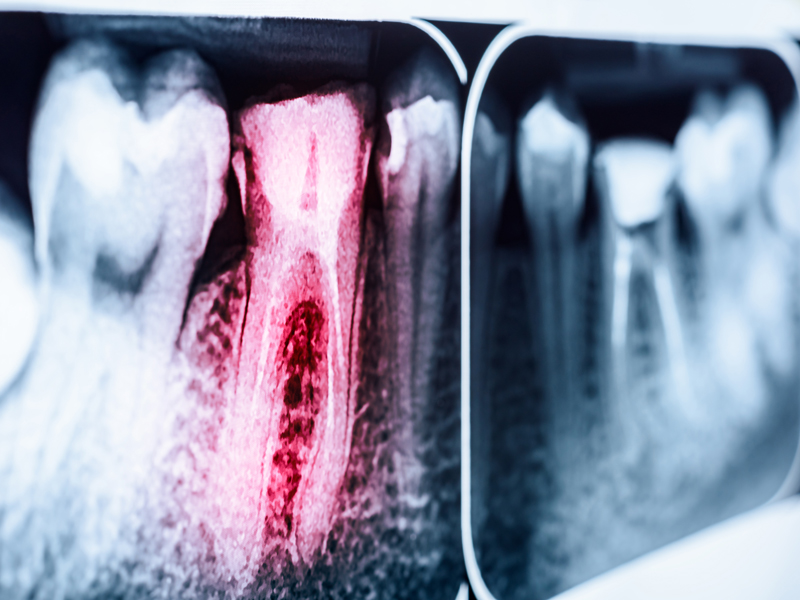

In vielen Fällen verursacht eine Entzündung im Wurzelkanal keinerlei Schmerzen und verläuft somit unbemerkt. Dies tritt auf, wenn die Nerven im Zahn nicht mehr auf Reize reagieren, ein Zustand, der oft als „toter Zahn” missverstanden wird. Durch frühzeitige Erkennung und Ausschaltung der Ursachen, wie zum Beispiel Karies, lassen sich Entzündungen oftmals effektiv vermeiden, was die Wahrscheinlichkeit einer vollständigen Erholung des Zahnes ohne bleibende Schäden deutlich erhöht. Wird eine Entzündung jedoch ignoriert, kann sie zu eitrigen Abszessen an der Spitze der Zahnwurzel führen. In solchen Fällen ist meist eine Wurzelkanalbehandlung notwendig, um die Entzündung zu bekämpfen und den Zahn zu retten.

Sind in den Seitenkanälen der Wurzelspitze Bakterien oder eine Entzündung noch immer vorhanden, muss eine Wurzelspitzenresektion durchgeführt werden. Nur so kann die Infektionsquelle beseitigt und der Zahnverlust vermieden werden. Die Wurzelspitze wird dabei vom Kieferknochen aus entfernt und die Wurzelkanäle werden von unten verschlossen. Der Zahn kann im Kieferknochen erhalten bleiben.